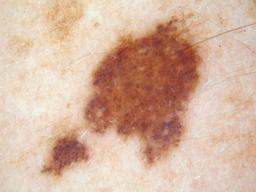

Training set from the ISIC 2016 Challenge. The "Skin Lesion Analysis Towards Melanoma Detection" challenge leverages a dataset of annotated skin lesion images from the ISIC Archive, The dataset contains a representative mix of images of both malignant and benign skin lesions.

{

"age_approx": 45,

"anatom_site_general": "anterior torso",

"clin_size_long_diam_mm": "4.50",

"concomitant_biopsy": true,

"diagnosis_1": "Malignant",

"diagnosis_2": "Malignant melanocytic proliferations (Melanoma)",

"diagnosis_3": "Melanoma in situ",

"diagnosis_confirm_type": "histopathology",

"family_hx_mm": false,

"image_type": "dermoscopic",

"melanocytic": true,

"personal_hx_mm": false,

"sex": "female"

}